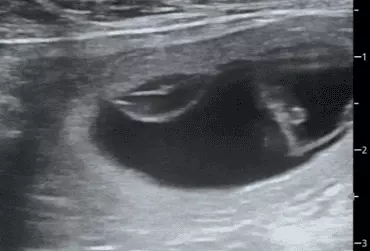

W literaturze opisano niewiele przypadków ciąż bliźniaczych jednokosmówkowych u suk. W trakcie wczesnej diagnostyki ultrasonograficznej ciąży u suki rasy whippet (chart angielski) zobrazowano pęcherz ciążowy, w którym znajdowały się dwa zarodki. Podczas badań kontrol­nych zarodki, a później płody wykazywały prawidłową organogenezę i żywotność. Ich rozwój przebiegał podobnie względem pozostałych ośmiu płodów. W 63. dniu ciąży wykonano zabieg cesarskiego cięcia i wydobyto dwa płody tej samej płci, o bardzo podobnym wyglądzie, z dwóch pęcherzy płodowych przyczepionych do jednego łożyska, oraz pozostałe osiem płodów.

Ryzyko związane z ciążą bliźniaczą jednokosmówkową u ciężarnych suk nadal jest nieznane, istnieją jednak doniesienia o śmierci płodu lub płodów w ciążach jednokosmówkowych u tego gatunku. Badanie ultrasonograficzne w czasie ciąży pozwala na wczesne rozpoznanie ciąży jednokosmówkowej, a monitorowanie żywotności płodów może ograniczyć ryzyko powikłań położniczych i przynieść korzyści zdrowotne zarówno samicy, jak i rodzeństwu z miotu.